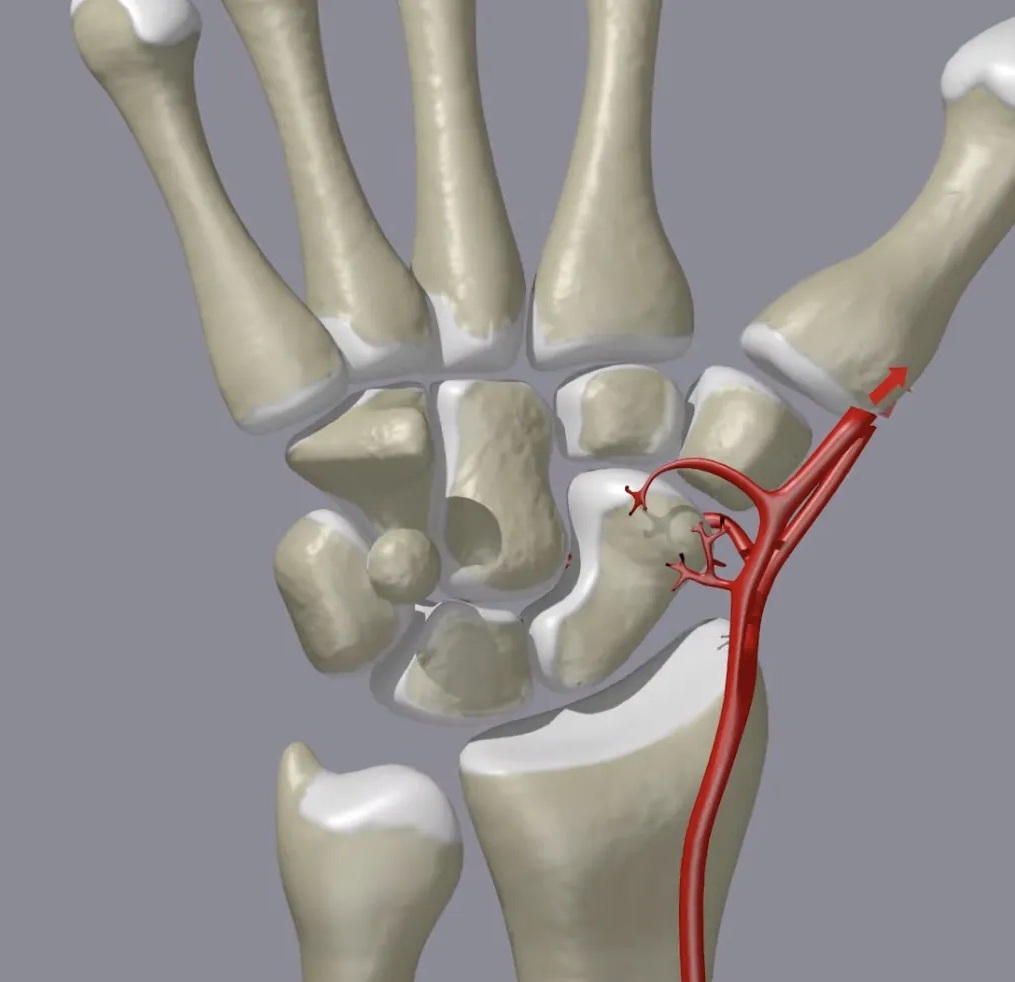

Fall on an outstretched hand with wrist pain… 👀 This is one of the most commonly missed fractures. You shouldn’t miss it on this xray. Can you name this fracture? Read: wikism.org/Scaphoid_Fract… #orthopedics #radiology #xray #mededucation #sportsmedicine #emergencymedicine

MedEd_Cases's tweet image. Fall on an outstretched hand with wrist pain… 👀

This is one of the most commonly missed fractures.

You shouldn’t miss it on this xray.

Can you name this fracture?

Read: wikism.org/Scaphoid_Fract…

#orthopedics #radiology #xray #mededucation #sportsmedicine #emergencymedicine